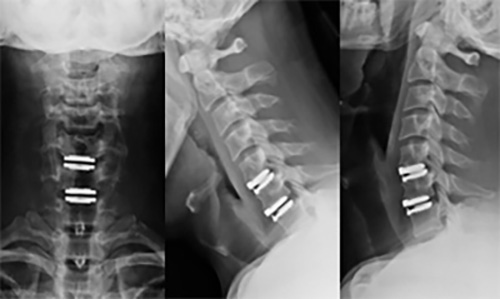

우선 목디스크란 목뼈 사이의 디스크가 손상되어 발생하는 질환을 의미합니다. 디스크는 척추뼈 사이에서 충격을 흡수하고 신경을 보호하는 역할을 하는데, 디스크가 손상되면 신경이 압박되어 통증, 저림, 마비 등의 증상이 나타납니다.

하지만 증상이 심하지 않은 경우, 보존적 치료를 통해 호전될 수 있습니다. 보존적 치료에는 휴식, 약물치료, 물리치료, 운동치료 등이 있습니다. 그러나 증상이 심한 경우에는 수술이 필요할 수 있습니다.